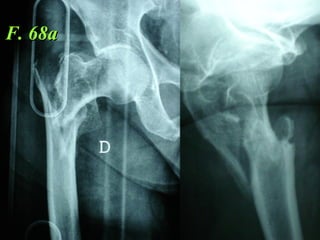

F. 68a